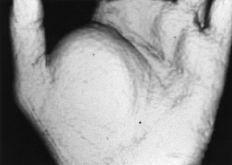

Los tumores glómicos tienen una localización pulpar, y más concretamente subungueal.2,6,20,22,24-27,34,38,39 En esta serie hubo nueve casos de localización pulpar, de los cuales siete fueron subungueales. Sin embargo, cabe la posibilidad de TPB subungueales que no son tumores glómicos, como un hidroadenoma nodular no incluido en la serie por haber sido tratado fuera de los períodos de estudio. El tumor glómico es una tumoración procedente de la proliferación del glomus mioarterial, anastomosis arterio-venosa con un lecho capilar intermedio que no está presente al nacimiento y se desarrolla en los primeros años de la vida. Las estructuras vasculares están envueltas por numerosas fibras musculares y nerviosas, tanto mielínicas como amielínicas. El cuerpo glómico está rodeado por una cápsula fibrosa. La función principal del glomus es la regulación de la temperatura corporal y la tensión arterial mediante la apertura y cierre de sus anastomosis. Los tumores glómicos se diagnostican cuando su tamaño es superior a 1 mm. La etiología se supone traumática, aunque no está demostrado. Clínicamente se caracterizan por dolor intenso a la presión local, intolerancia al frío, y deformidad, reblandecimiento y decoloración subungueales. En la radiografía convencional, y característicamente en la de alta definición, puede apreciarse una erosión subungueal en los casos de esta localización (Fig. 2).1,2,6,17,24,25,38,39

Figura 2. Tumor glómico subungual. A y B: Rx PA y lateral del extremo del dedo afecto. Obsérvese la erosión ósea (flechas).